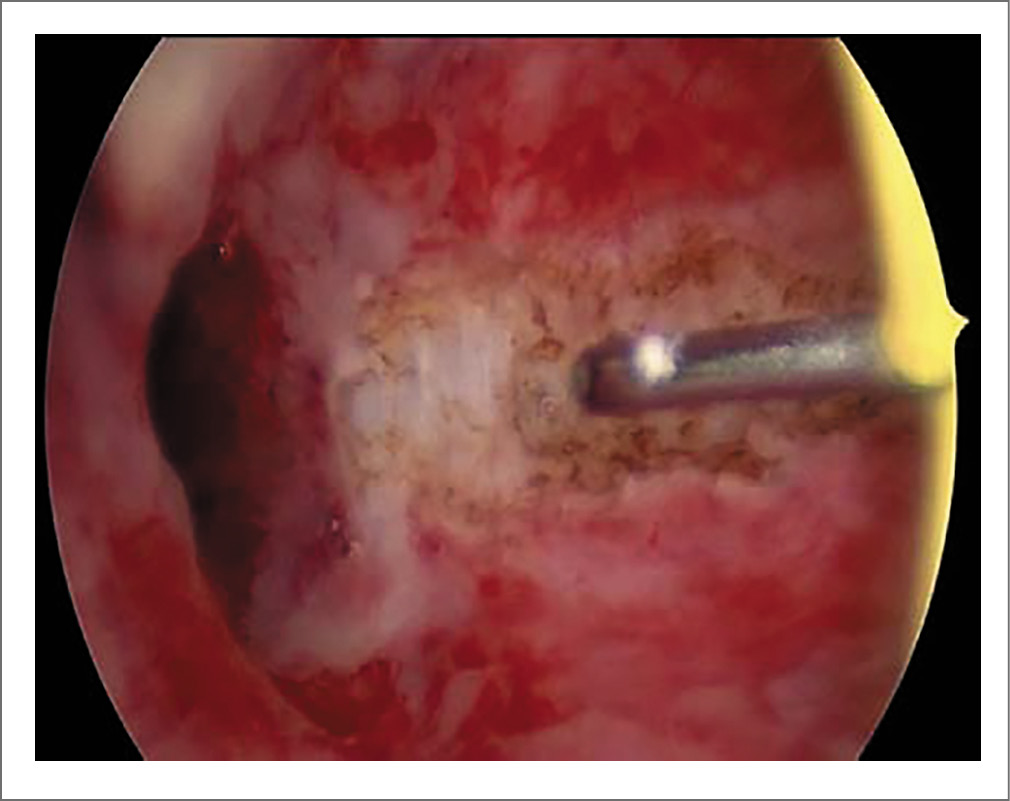

Патоморфологическое исследование операционного материала показало туберкулезное воспаление с очагами некроза, окруженное зоной фиброза (рис. 6). Важный нюанс: исследование соскоба эндометрия не продемонстрировало гистологических изменений, характерных для туберкулеза; идентифицировать патоген в соскобе также не удалось. Вместе с тем в резецированных тканях яичника методами молекулярно-генетической диагностики обнаружена МБТ.

Рис. 6. Туберкулез яичника. Крупные сливающиеся участки казеозного некроза, окруженные эпителиоидно- и гигантоклеточным валом, зоной продуктивной мононуклеарной инфильтрации и фиброза, с вытеснением железистых структур. Ув. 40. Окраска гематоксилином и эозином. Источник: собственное наблюдение (фото П.Н. Филимонова). / Fig. 6. Ovarian tuberculosis. Large confluent areas of caseous necrosis surrounded by an epithelioid and giant cells shaft, a zone of productive mononuclear infiltration and fibrosis, with a displacement of glandular structures. 40×. Hematoxylin and eosin staining. Source: authors’ observation (photo by P.N. Filimonov).